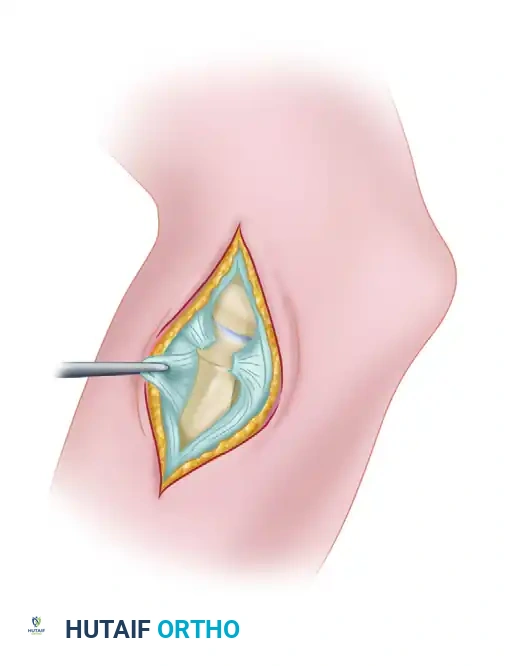

The Supine Suspended Position

With the patient supine, the hand and forearm are placed in a sterile, waterproof stockinette suspension device. This is connected to a rope and pulley system utilizing 5 to 6 lbs of weight to provide balanced suspension.

The patient is positioned so the arm hangs free off the side of the operating table. The shoulder is placed in neutral rotation and 90 degrees of abduction, while the elbow is flexed at 90 degrees.

Advantages of the Supine Position:

* Provides excellent access to both the medial and lateral sides of the elbow.

* The 90-degree flexion relaxes the anterior neurovascular structures in the antecubital fossa, allowing them to fall away from the joint capsule.

The Carson Modification: To eliminate the need for an overhead suspension system, Carson described utilizing two small arm boards placed side-by-side and attached to the operating table at shoulder level. The arm rests on this platform, and an assistant supports the hand upright. This stabilizes the elbow, preventing it from swinging in space, while the narrowness of the boards ensures unobstructed maneuvering of the arthroscope.